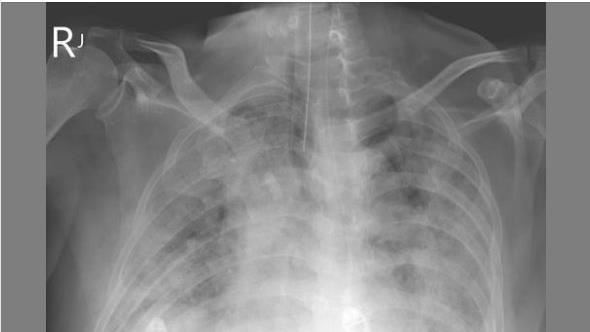

蘇一峰醫師在個人臉書發文並貼出一張「大白肺」X光片,他表示,從中國回來的60歲台商大白肺(嚴重肺炎)了,該名台商回來3天自己驗後確診新冠,可是沒有第一時間就醫,之後雖給抗病毒藥物,還是擋不住進展,「氧氣已用到百分之百」,現在插管病危。他並呼籲指揮中心,可驗看看這名台商患者的病毒株是哪一種,避免未知新病毒侵台外,也可考慮若從中國返台民眾若確診症狀較嚴重者,也都檢驗病毒株。(記者:簡浩正)